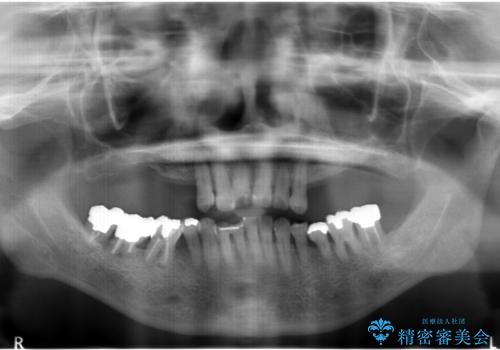

- 上の奥歯がないまま長年過ごしていたら前歯もぐらぐらしてきてしまったことを主訴に来院された患者様です。

奥歯の咬み合わせがないことにより前歯に負担がかかり動揺が出ていました。

精査したところ右下の奥歯も歯周病により保存不可能な状態でした。

なるべく予算を抑えたいとのご希望から、上顎は入れ歯、右下臼歯部はインプラントによる治療を行いました。

上の前歯は動揺を抑え、入れ歯の着脱にも耐えうるように被せ物を連結させることにしました。

しっかりと咬むことができるようになり喜んで頂けました。

全体的な歯の動揺もなくなり安心して頂けました。

4年経過しましたが問題なく調子が良いとおっしゃって下さいました。